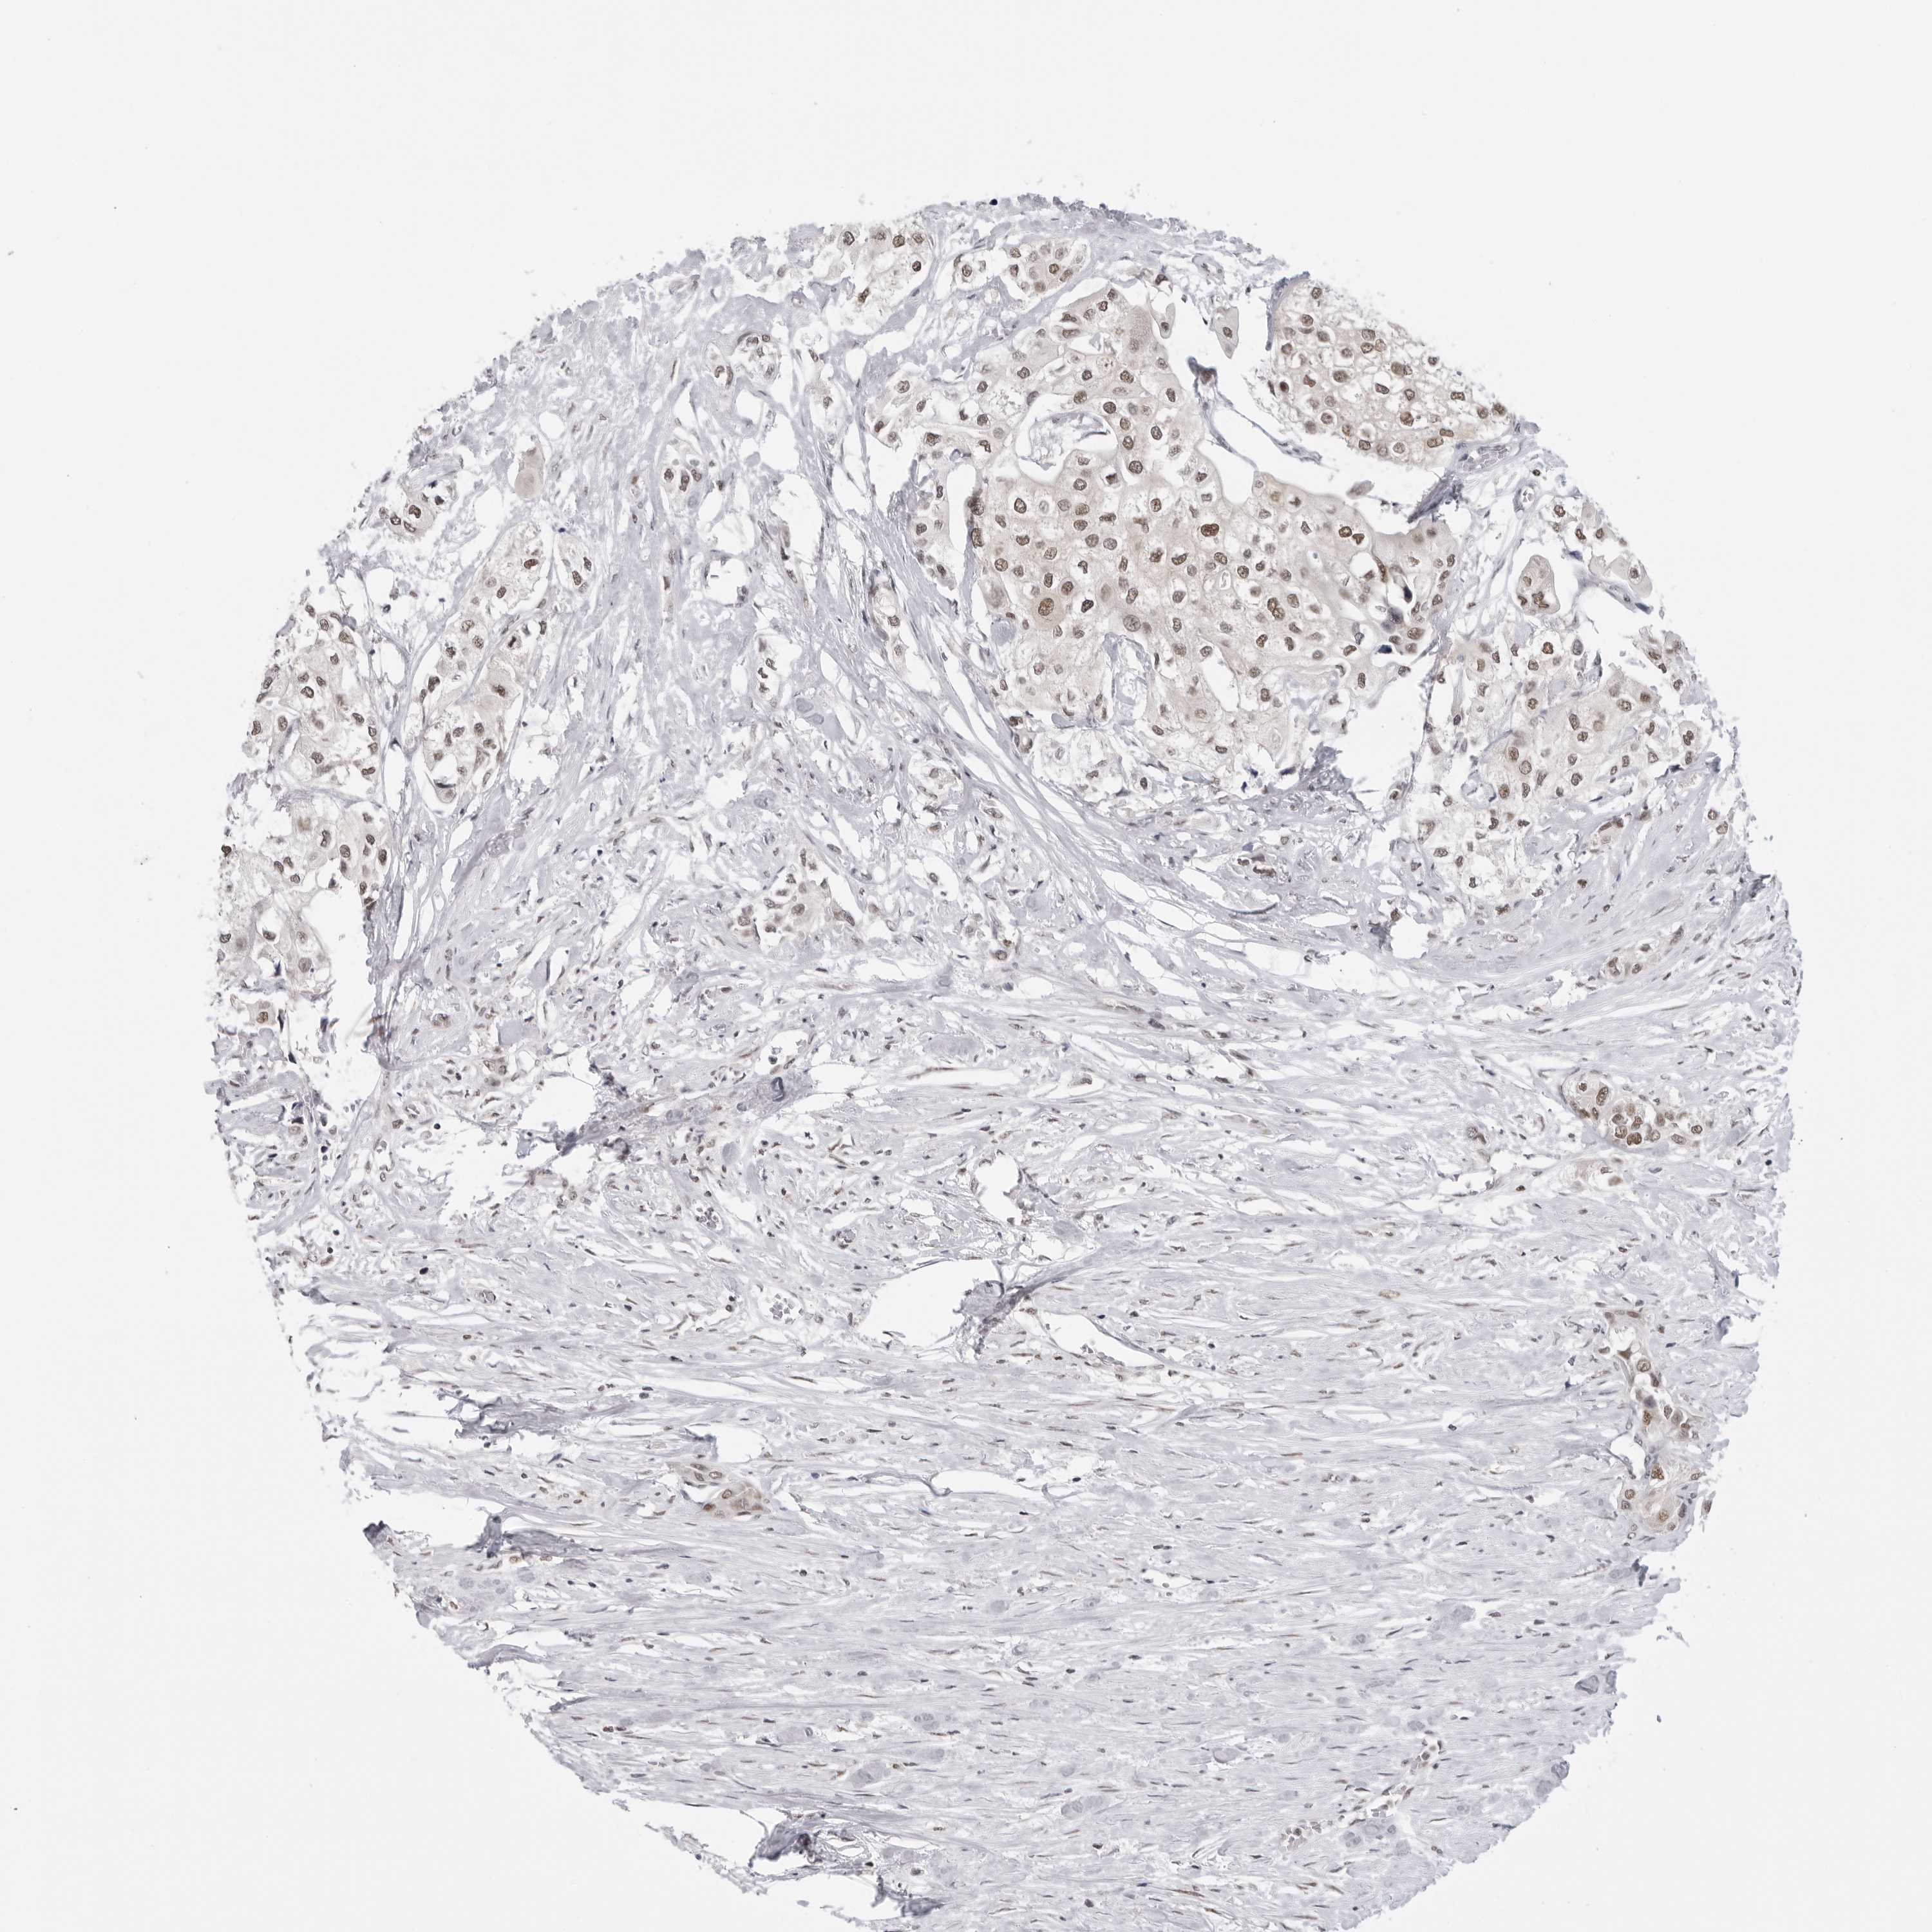

UROTHELIAL CANCER - Protein expressioni

A mouse-over function shows sample information and annotation data. Click on an image to view it in a full screen mode. Samples can be filtered based on level of antibody staining by selecting one or several of the following categories: high, medium, low and not detected. The assay and annotation is described here.

Antibody stainingi

Antibody staining in the annotated cell types in the current human tissue is reported as not detected, low, medium, or high, based on conventional immunohistochemistry profiling in selected tissues. This score is based on the combination of the staining intensity and fraction of stained cells.

Each image is clickable and will lead to virtual microscopy that enables deeper exploration of all samples and also displays staining intensity scores, fraction scores and subcellular localization as well as patient and tissue information for each sample.

Antibody HPA026306

Antibody HPA026309

Antibody CAB016538

Staining

High

Medium

Low

Not detected

Intensity

Strong

Moderate

Weak

Negative

Quantity

>75%

75%-25%

<25%

None

Location

Nuclear

Cytoplasmic/membranous

Cytoplasmic/membranous,nuclear

Urothelial carcinoma, Low grade

Urothelial carcinoma, High grade